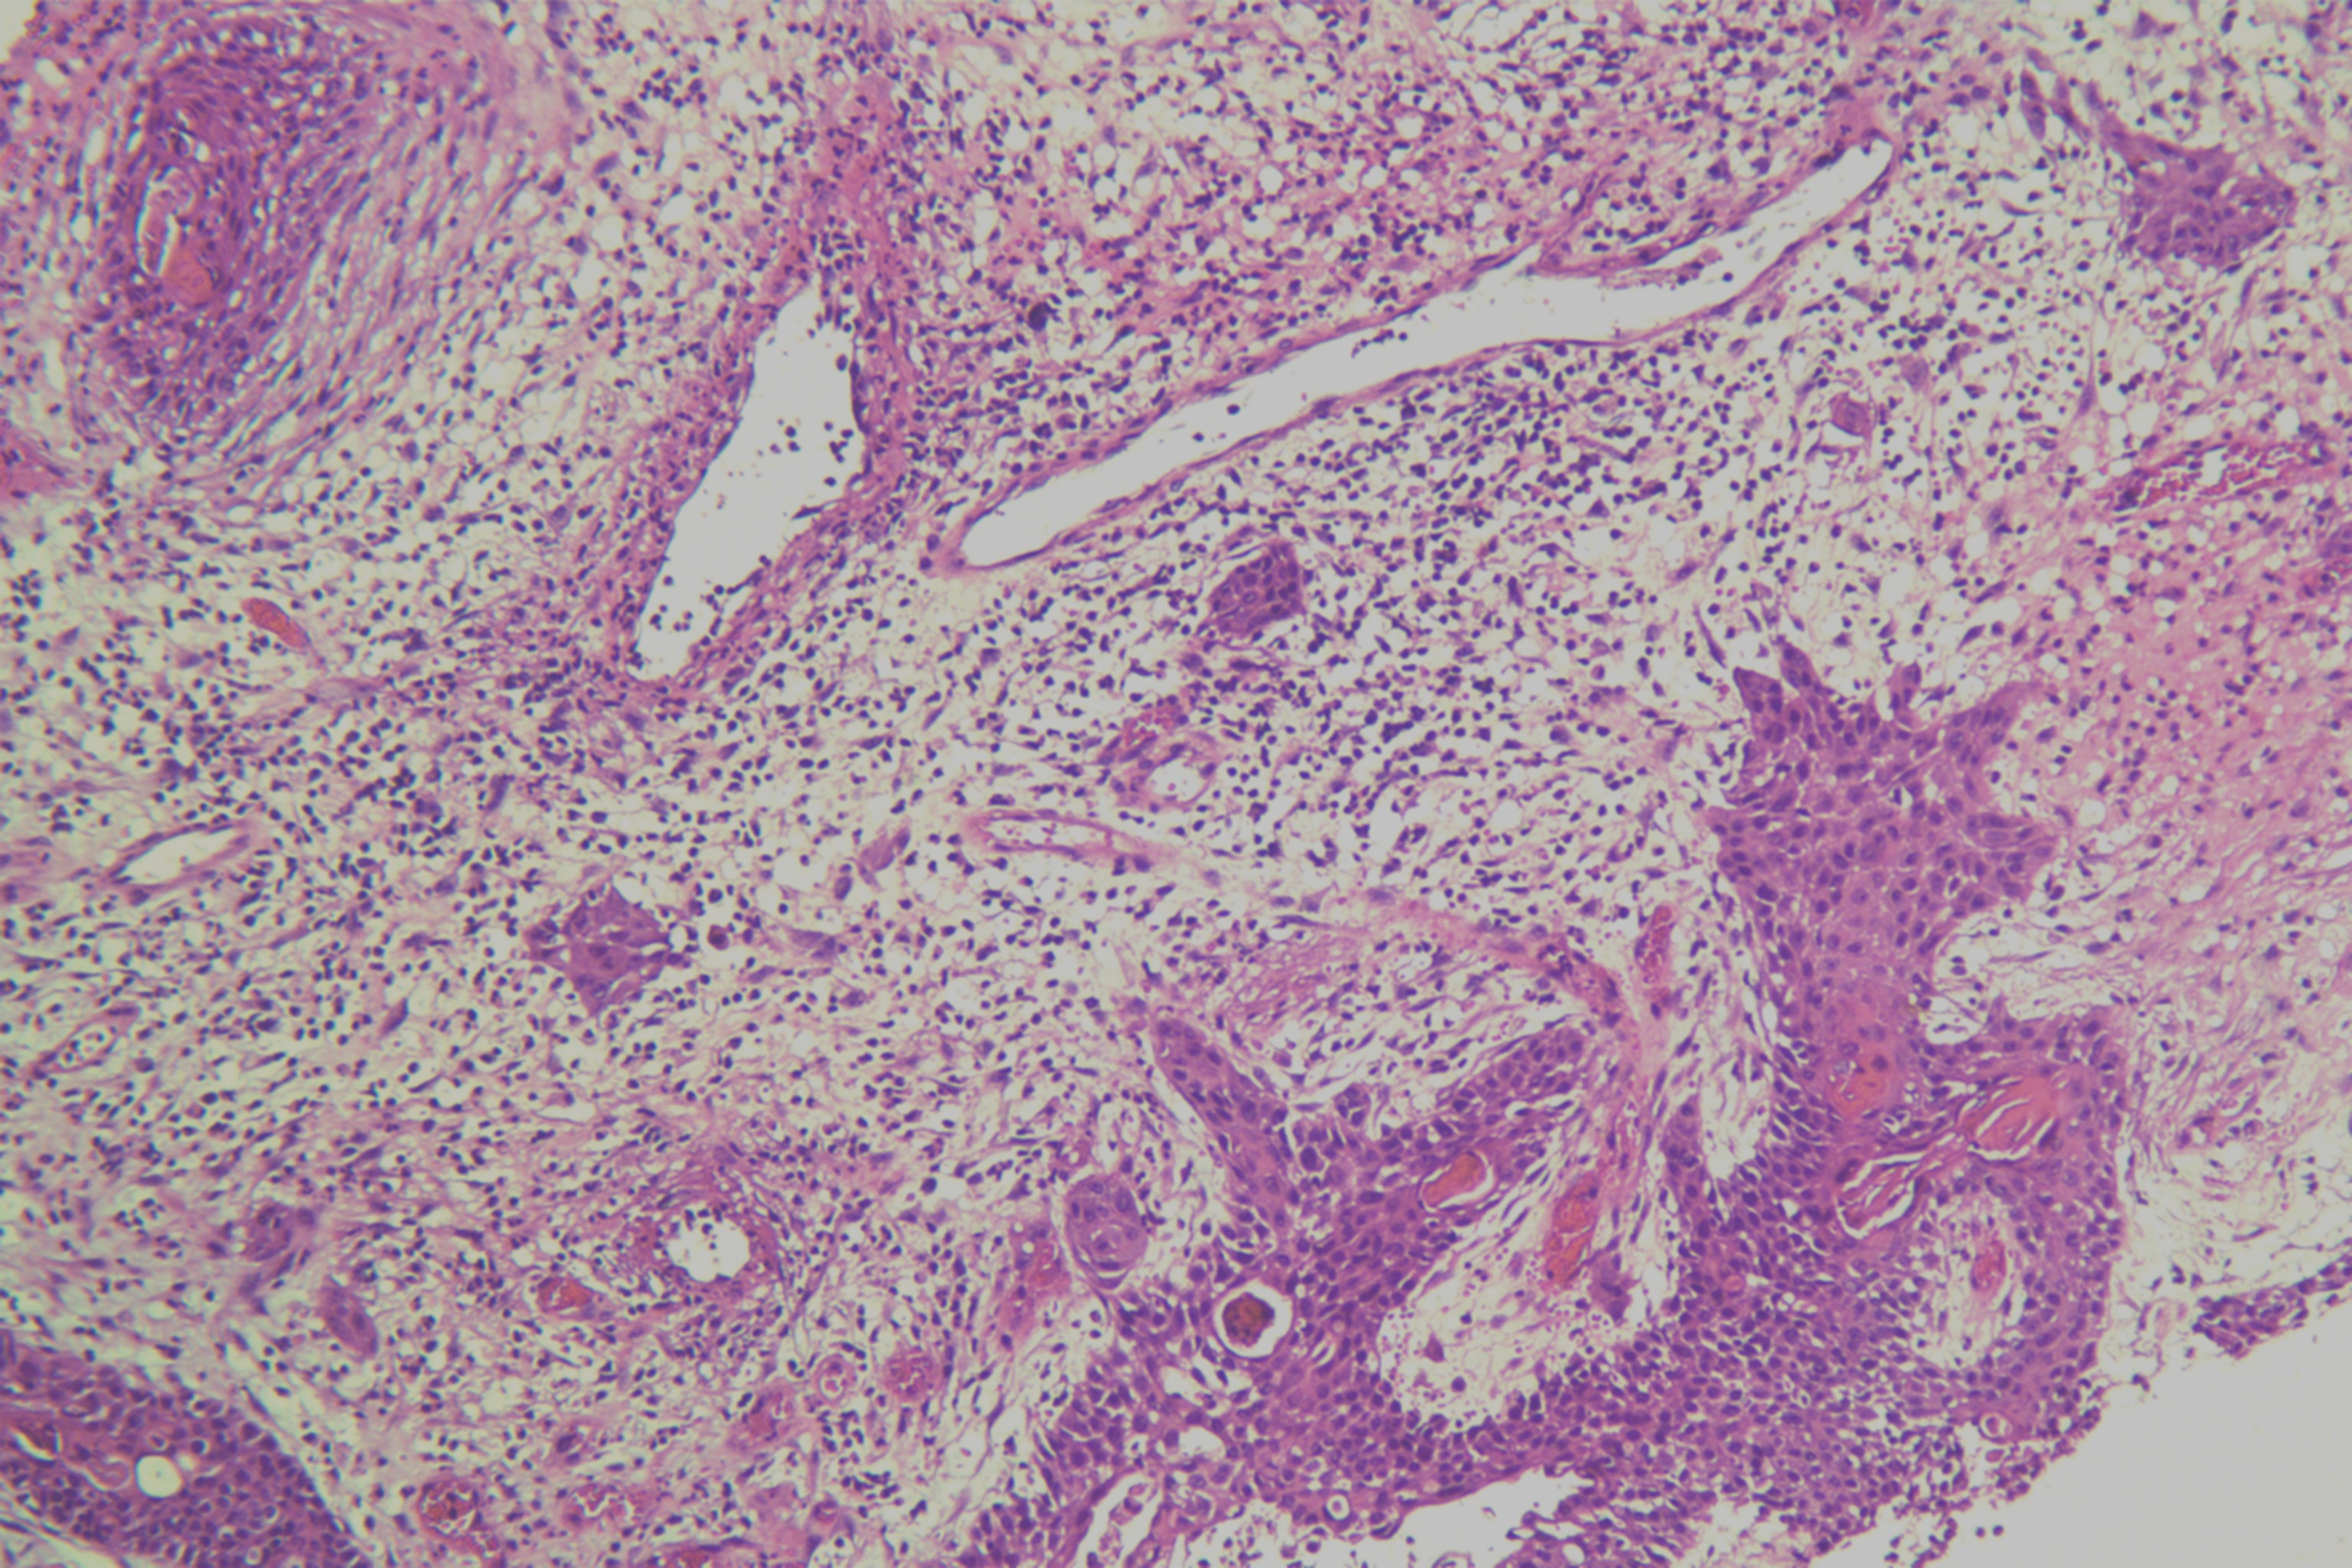

鳞癌?

性别

男

年龄

68岁

头皮肿物20年,包块逐渐增大,反复破溃

头皮肿物(局部活检)

1.5*1*0.3cm灰红碎组织一堆

考虑:基底细胞癌